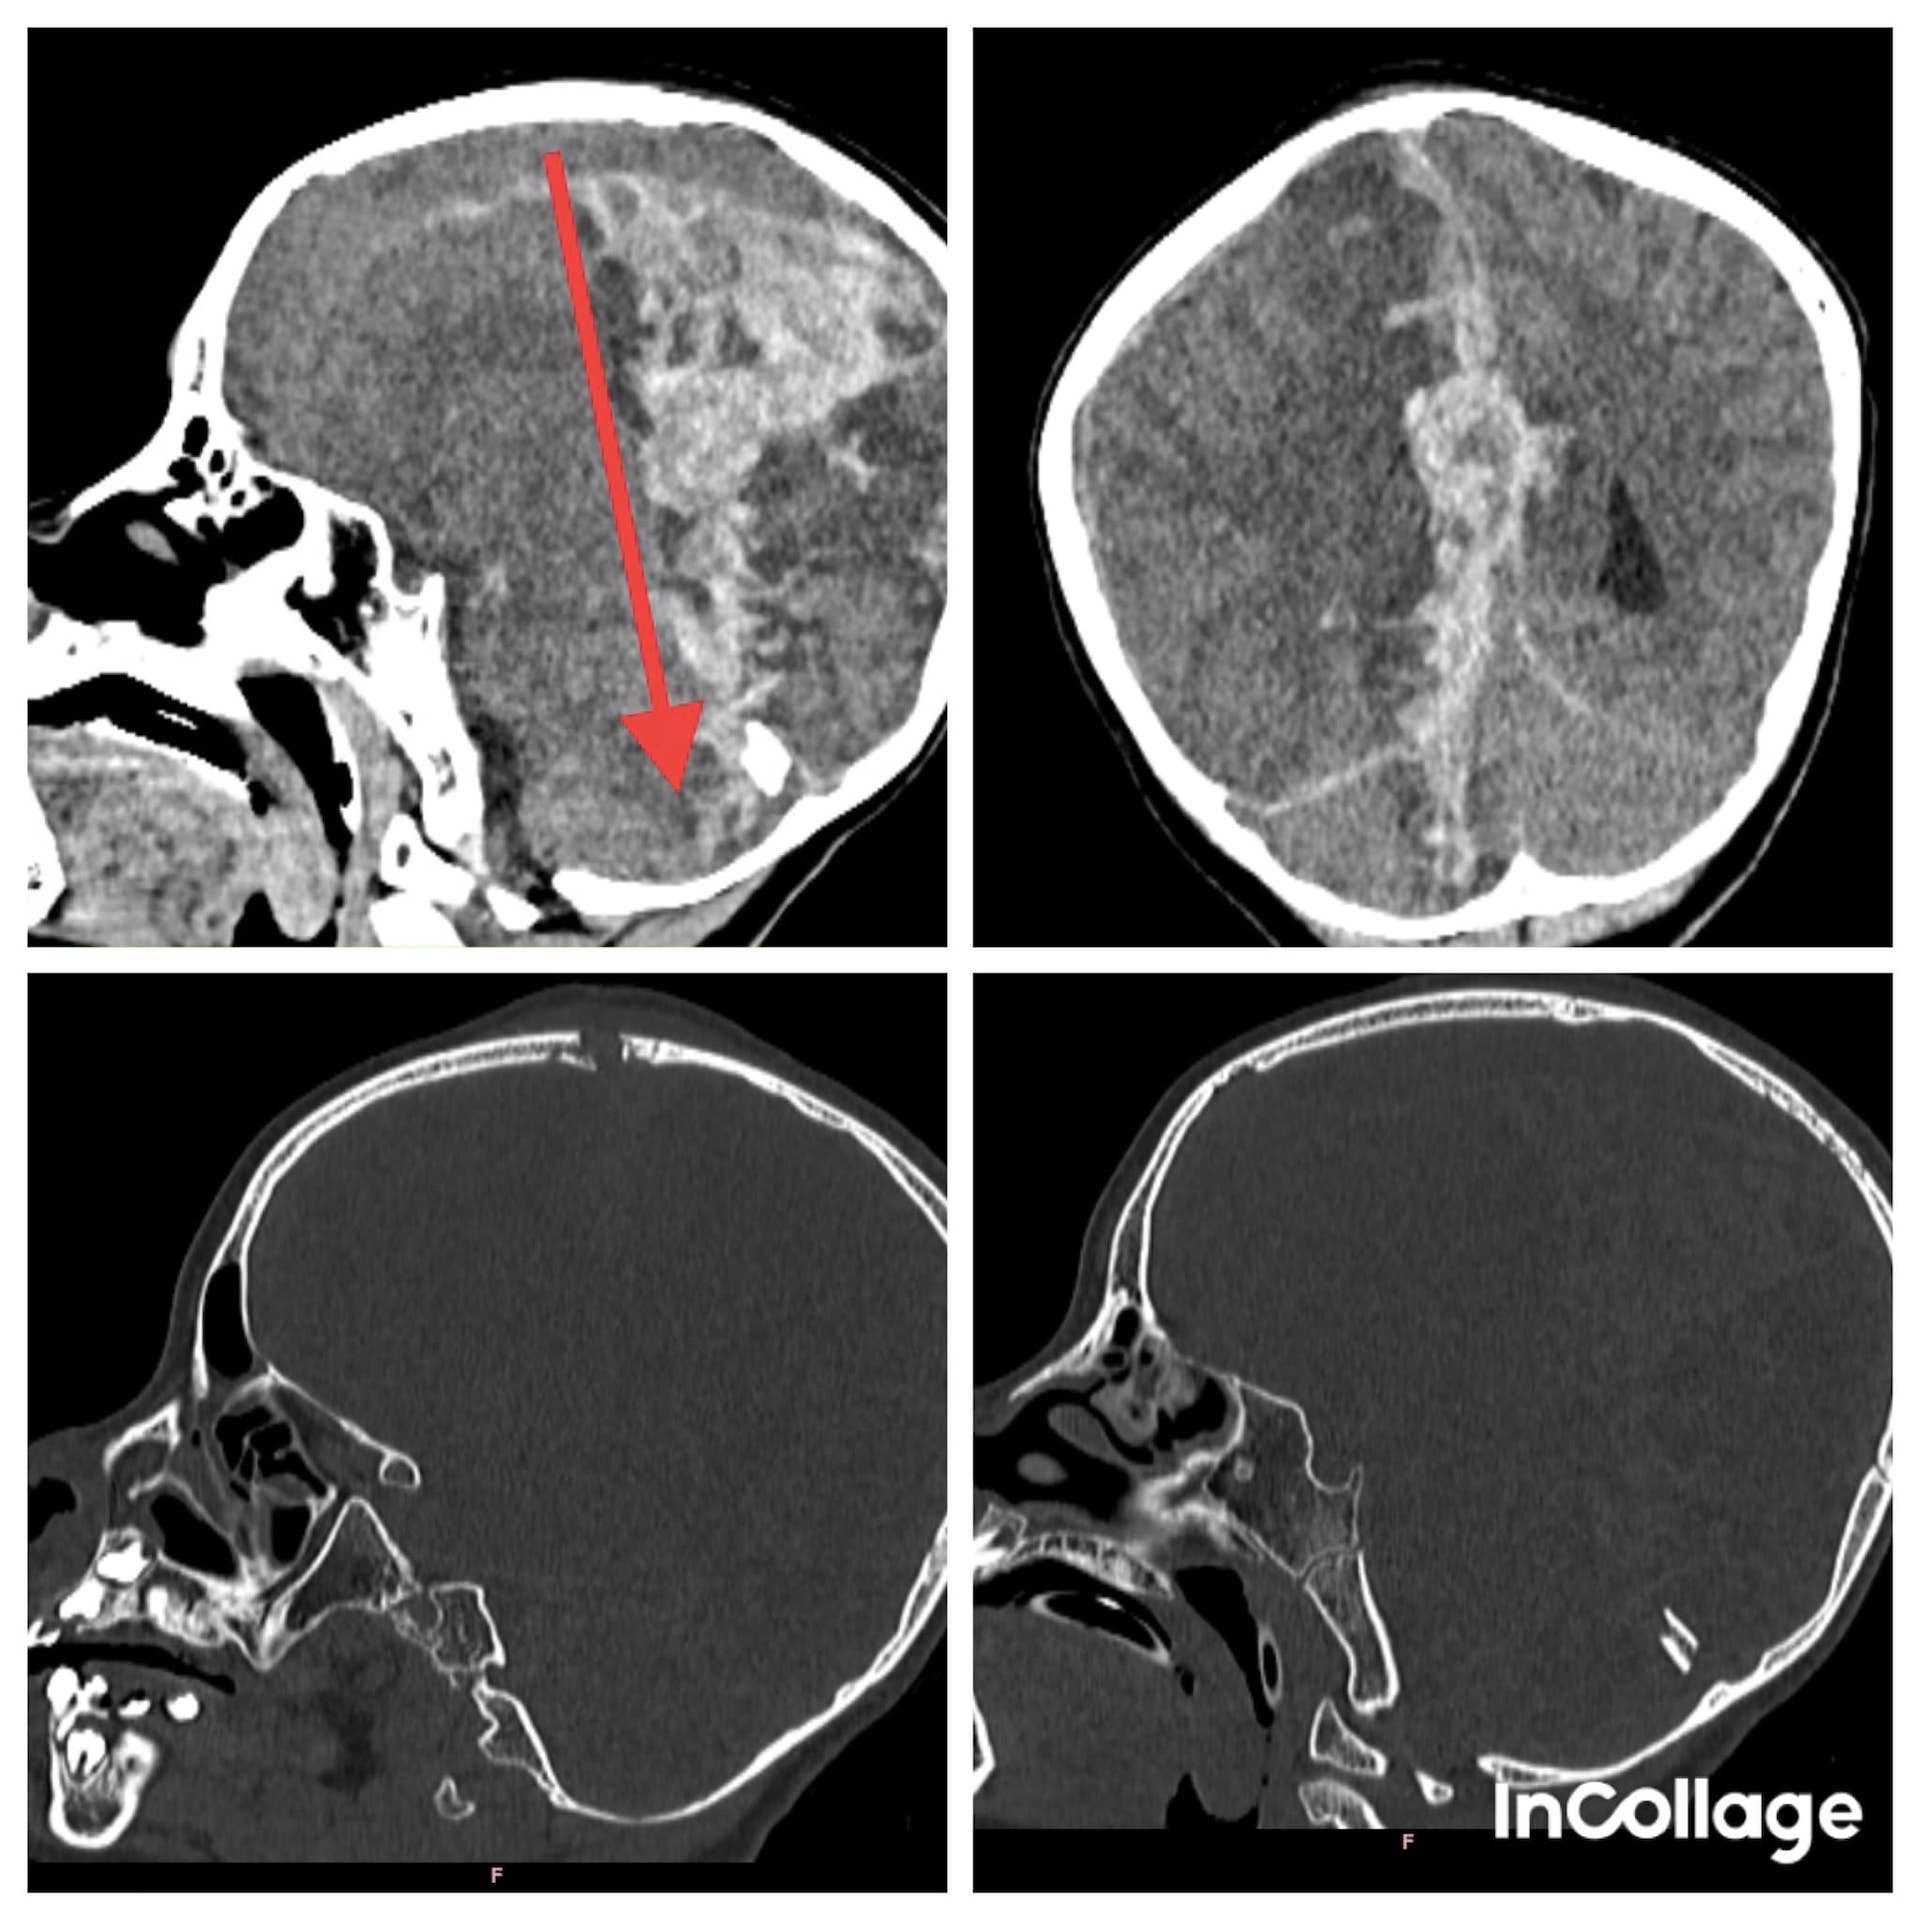

Mọi người đưa nạn nhân đến bệnh viện sơ cứu rồi chuyển lên TP.HCM tiếp tục điều trị. Tại Bệnh viện Nhi đồng 2 TP.HCM, ê-kíp cấp cứu ghi nhận bé hôn mê sâu, có vết thương trước đỉnh đầu đã được khâu, CT-scan ghi nhận tổn thương xuyên thấu qua não.

Tổn thương từ phía trước đỉnh đầu xuyên ra đến phần tiểu não phía sau, gây xuất huyết dưới màng cứng và trong não lượng nhiều, chèn ép và phù não. Sau khi tiếp nhận, bệnh viện ngay lập tức thực hiện phẫu thuật khẩn cấp để lấy máu tụ và mở sọ giải áp cho nạn nhân.